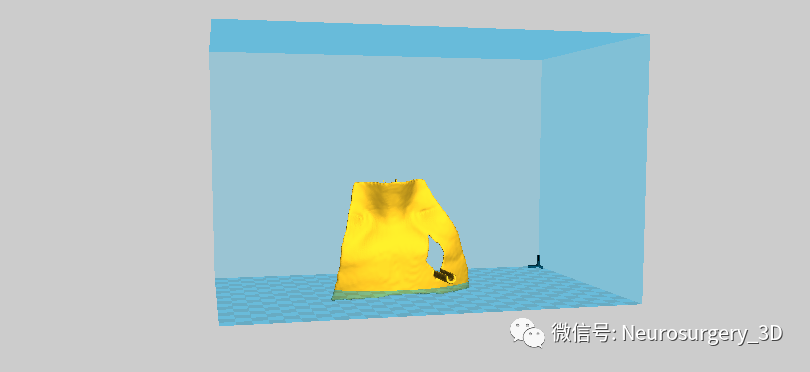

5、修剪需要打印的穿刺导板

6、以STL格式保存于电脑桌面上

7、传输到CURA切片软件

8、由以上穿刺导板制作过程可以看出,穿刺导板应用Scissors小剪刀剪切修剪导板,其边缘并不规则,可把本节第四步生成穿刺导板面具后提前导出并保存于桌面上。

9、把生成穿刺导板面具的STL导入到Mimics软件中,应用Simulate剪切成规则需要模型。